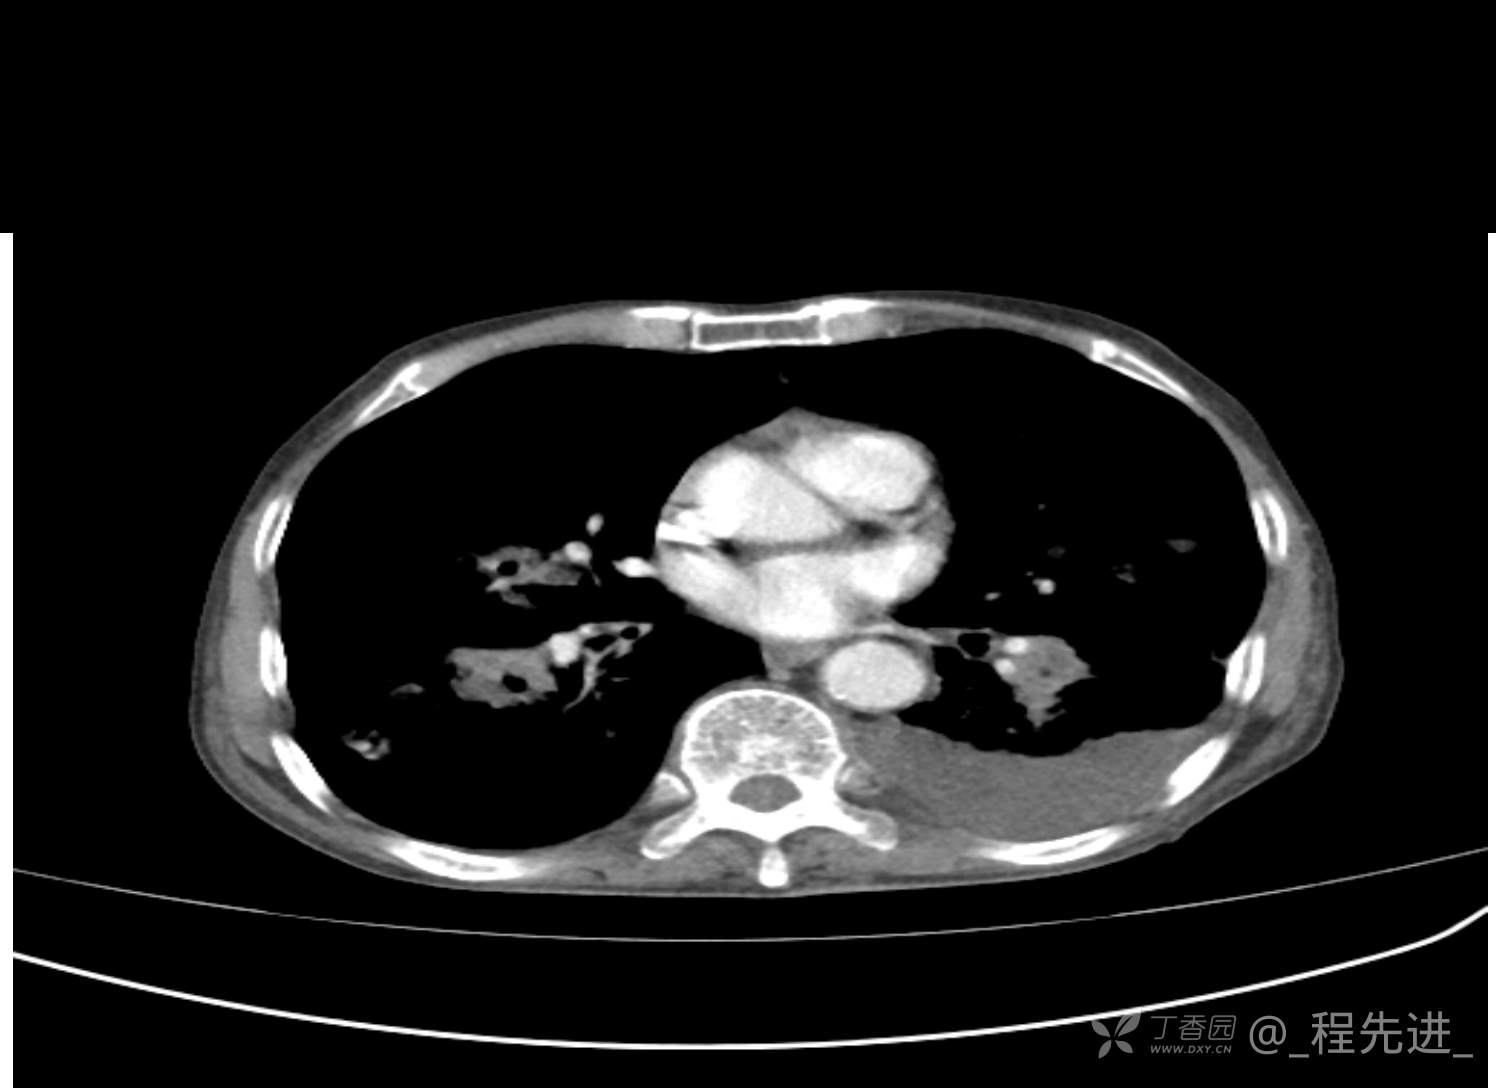

患者性别:男

患者年龄:81岁

简要病史:反复咳嗽、咳痰20余年,加重1周。两肺呼吸音低,可闻及散在干湿啰音。